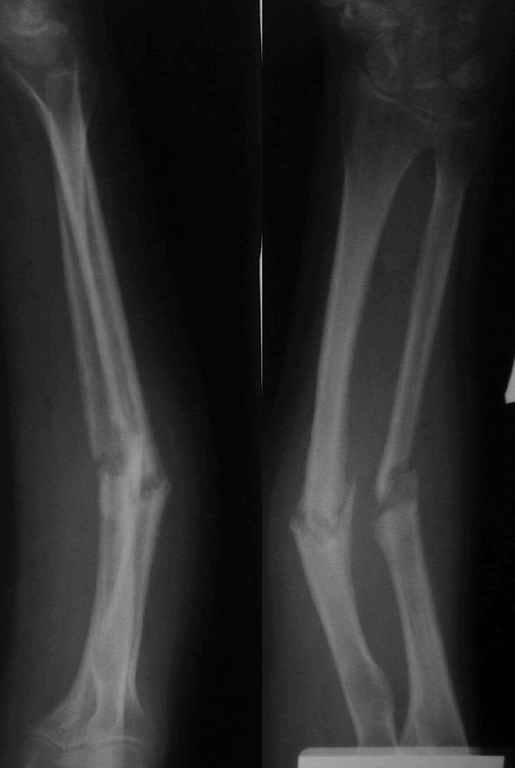

Уважаемые коллеги!У нас в травматологическом отделении клиник кафедры травматологии Самарского медуниверситета находится пациентка с ложными суставами костей предплечья, после остеосинтеза спицами (8 месяцев).

Девушка молодая, аппарат внешней фиксации категорически не приемлет. Выполнен закрытый БИОС СнМ с расверливанием (сверлом 4,5 мм).Хотелось ознакомиться с вашими комментариями.

1.Послеоперационные снимки сделаны на разных уровнях, но в одной проекции. Что во второй?

2.До операции были правильные взаимоотношения в дистальном лучелоктевом сочленении, после - лучевая заметно длиннее.

3.Лучевая кость практически лишена физиологического изгиба. Обусловлено это тем, что стержень не был соответсвующим образом изогнут, и спрямил кость. Даже если ротационные взаимоотношения отломков правильные (что отнюдь не факт), будет ротационная контрактура. Для ориентира, к чему стремиться, стоило бы перед операцией сделать снимок противоположного предплечья в той же проекции - предплечье в нейтральном положении, ладонь вниз, локтвой сустав в профиль.

4.Целесообразность статического запирания гвоздей тут довольно сомнительна, хорошего контакта на стыке не видно, осбенно на локтевой.

Пытались ли дать компрессию, и каким образом?

5.В лучевой кости винты введены в тыльно-ладонном направлении, что подвергало риску сухожилия и сосуды.

6. В дистальном отделе локтевой кости винт раза в два длиннее, чем надо. Как меряете необходимую длину?

Спасибо.